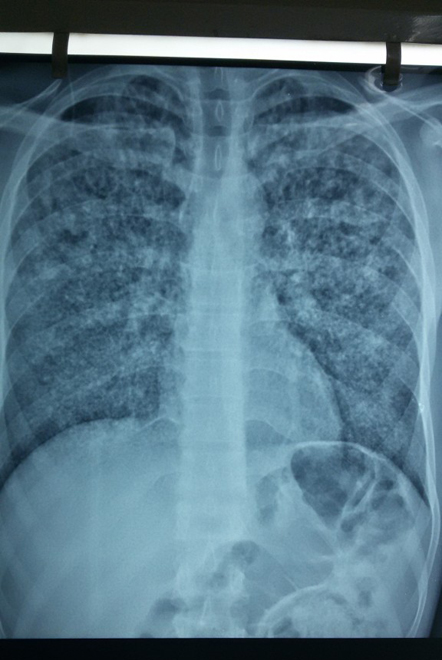

Την Παρασκευή (06/02/15) εξετάστηκε στο Κοινωνικό Ιατρείο νέος 24 χρονών από το Πακιστάν, ο οποίος ,μετά την κράτησή του στο Κέντρο Κράτησης μεταναστών στην Αμυγδαλέζα , παρουσίασε σταδιακή αδιαθεσία, απώλεια βάρους, πυρετό (40° C) και βήχα. Από την ακτινογραφία θώρακα διαγνώστηκε φυματίωση (κεχροειδής) .O ασθενής παραπέμφθηκε σε εφημερεύον νοσοκομείο της Αθήνας όπου και νοσηλεύεται.

Ακολουθεί η ακτινογραφία θώρακα